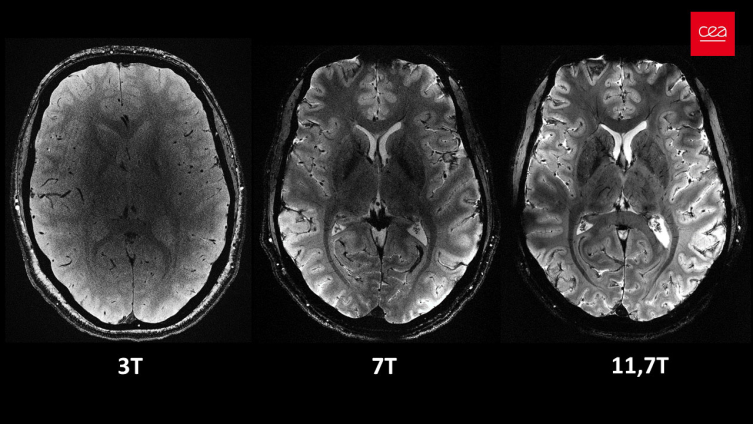

Yapılan çalışmalar kapsamında MRI cihazının son birkaç ay içerisinde yaklaşık 20 sağlıklı gönüllü üzerinde test edildiği kaydedilen açıklamada, neredeyse 4 dakikada en net beyin görüntüsünün elde edildiği aktarıldı.Açıklamada, 11,7 Tesla manyetik güce sahip Iseult MRI makinesiyle kısa sürede çekilen görüntülerin, hastanelerde yaygın kullanılan cihazlarla elde edilmesinin saatler sürebileceği kaydedildi.

Iseult MRI cihazı ile elde edilen ultra detaylı anatomik bilgilerin, Alzaymır ve Parkinson gibi hastalıkların teşhisinde yardımcı olması bekleniyor.